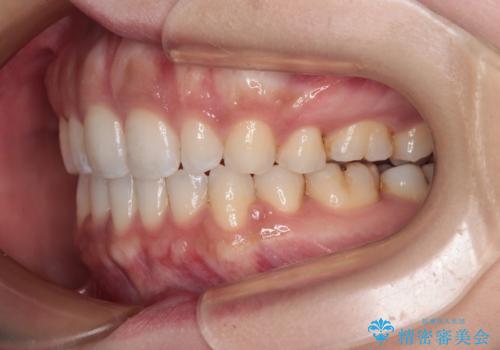

唇が閉じにくい ワイヤー装置での抜歯矯正

- 矯正装置

- クリアブラケット

上下ともに前歯が少し舌側に傾斜したような仕上がりとなりましたが、口が閉じやすくなったとのことで、患者様には大変満足していただけました。